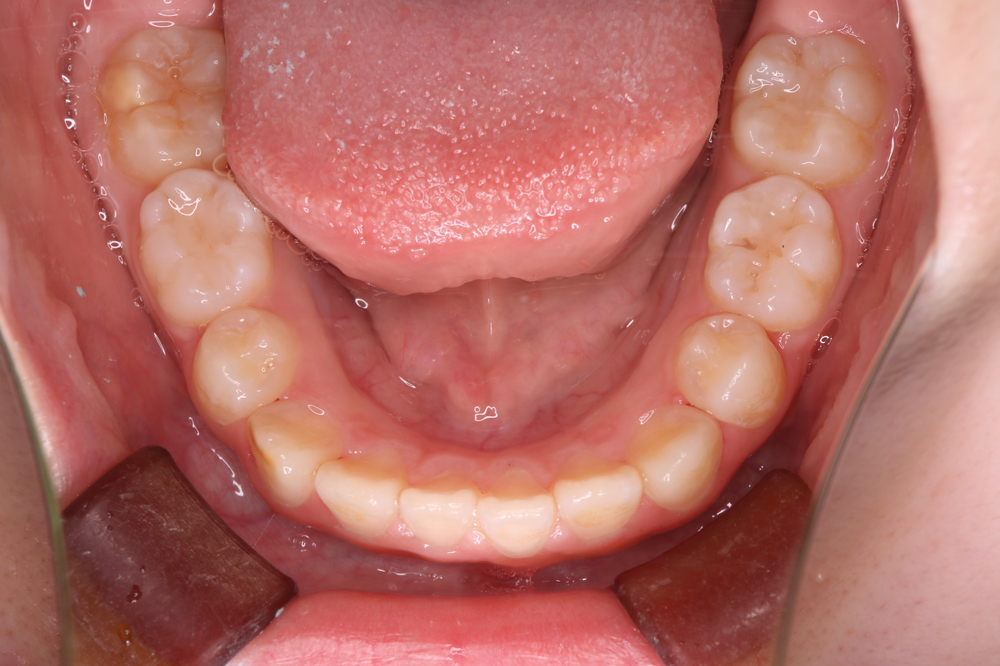

【下の歯】

これからリテーナー生活を続けながら、

第一期治療で獲得した上の写真のスペースをしっかり保ち、

娘の歯の成長を温かく見守っていきたいと思います。